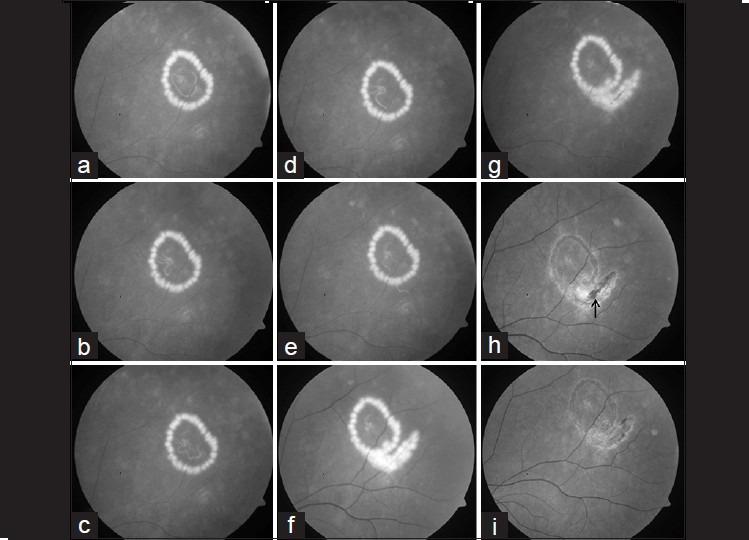

Live subretinal nematode: management by focal argon laser photocoagulation with spectral domain OCT analysis.

Indian J Ophthalmol. 2014 Aug;62(8):899-901. doi: 10.4103/0301-4738.141081.